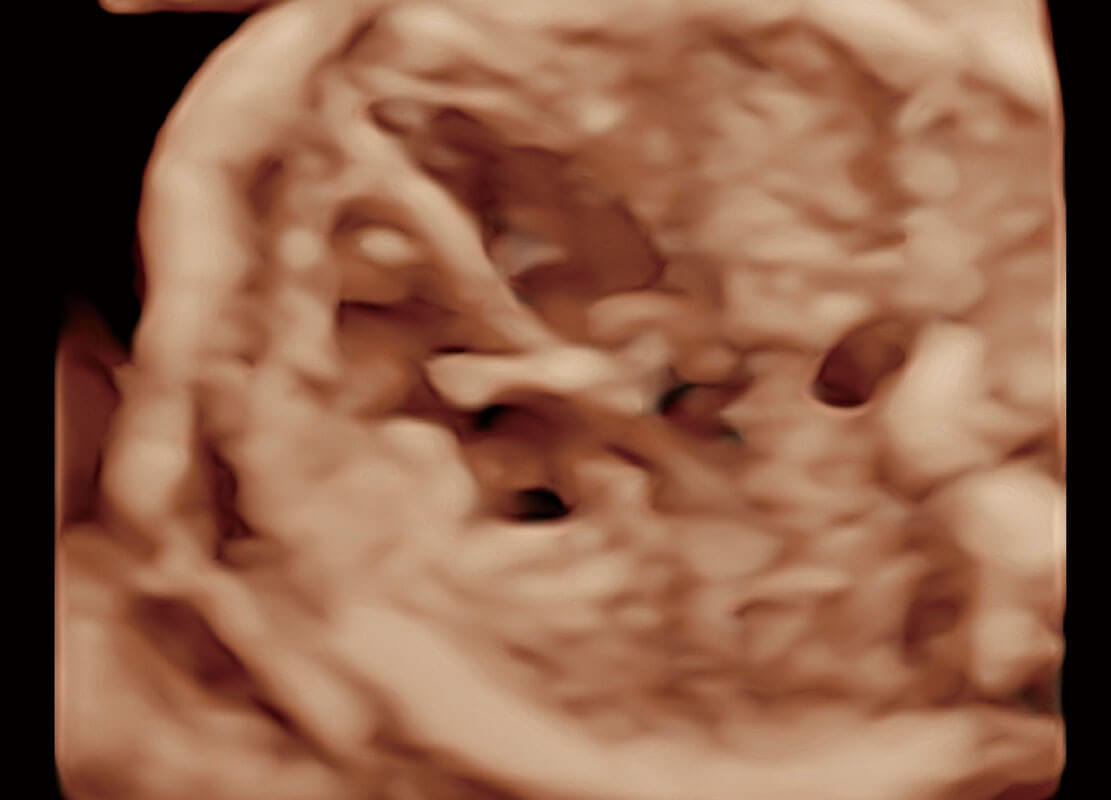

胎心筛查

P60搭载一系列胎儿心脏成像技术,实现精细的胎儿心脏评估。

• 四腔切面

• 胎心容积成像